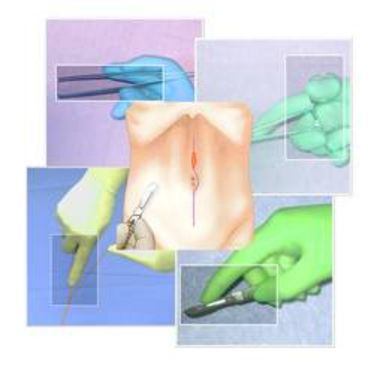

24.10.2013

BASIC SURGICAL SKILLS

BASIC SURGICAL SKILLS

BASIC SURGICAL SKILLS

BASIC SURGICAL SKILLS

BASIC SURGICAL SKILLS

BASIC SURGICAL SKILLS